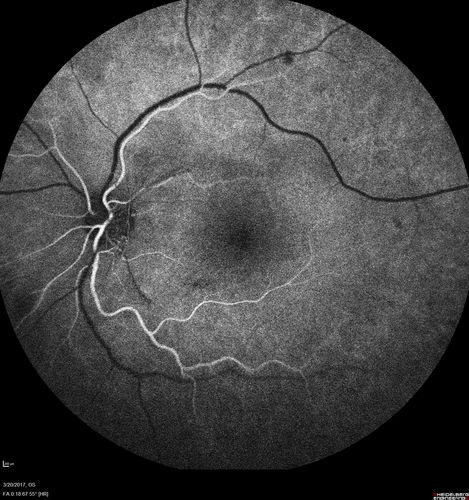

Proliferative Diabetic Retinopathy - NVD regressed with PRP laser

76 year old diabetic man - Presented one year ago with NVD in the left eye.  This regressed with laser but then a year later worsened.  Additional PRP was done and the NVD regressed again.